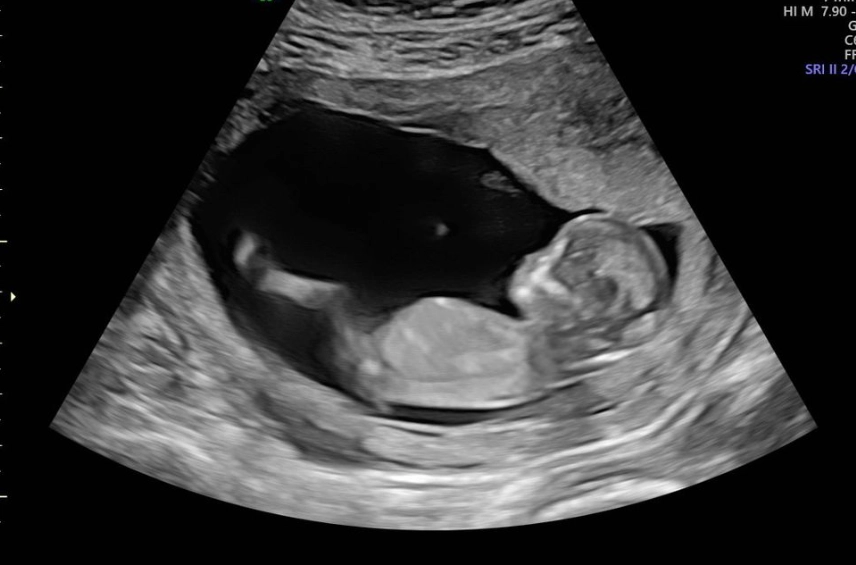

What Can You See on a 12-Week Ultrasound?

This is often the first detailed look at your baby, and it's breathtaking. The 12-week scan, sometimes combined with the First Trimester Screening (which assesses risk for chromosomal conditions), gives you a clear picture of that little occupant.

On the screen, you'll see your baby's location clearly within the amniotic sac inside the uterus. The sonographer will measure the baby from crown to rump to confirm your due date. They'll check for the presence of a nasal bone and measure the nuchal translucency—a small fluid space at the back of the baby's neck. An increased measurement can be a soft marker for certain conditions.

Beyond the medical checks, you'll get to see your baby in action. You might see the heart beating rapidly (around 120-160 beats per minute), watch the baby bring its hand to its mouth, or see it bounce gently against the uterine wall. It makes the whole thing feel wonderfully real.